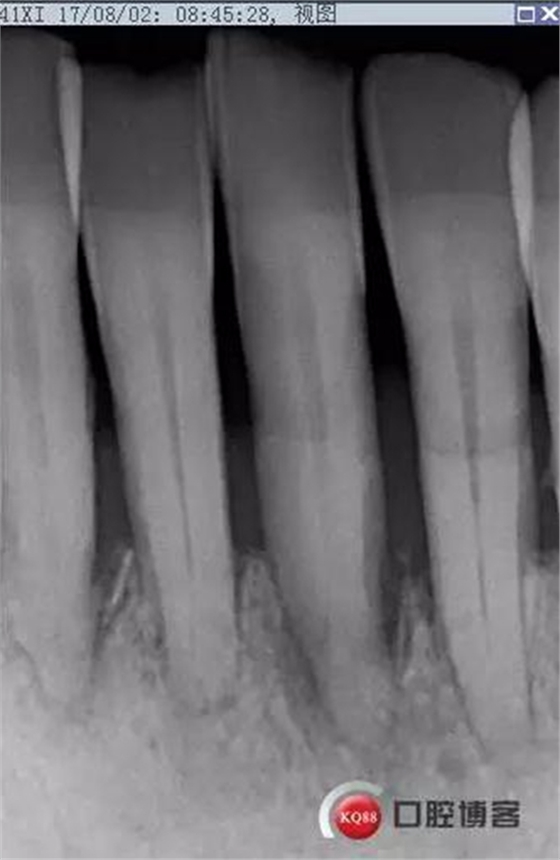

2017-08-02

檢查:下頜前牙區(qū)PD1-3mm,牙齦色澤尚可,舌側(cè)齦緣可見(jiàn)少量軟垢附著。31松II°,32、41、42松I°+。

X線(xiàn)示根周透射影骨密度增高。

處理:上橡皮障,31開(kāi)髓,測(cè)工作長(zhǎng)度17mm,含氯沖洗液沖洗,機(jī)擴(kuò)至04錐度30#,超聲蕩洗,一次性根充。33-43牙齒鄰接處super bond粘結(jié)固位,行松牙固定。調(diào)合。拍根充術(shù)后片,未達(dá)根尖,懷疑遺漏根管,去除根充物后,繼續(xù)探查根管,找到舌側(cè)根管,測(cè)長(zhǎng)度20mm,時(shí)間原因,未行擴(kuò)根,氫氧化鈣暫封。

圖省事,沒(méi)有拍術(shù)中試尖片,導(dǎo)致術(shù)后重新去除根充物,再次探查,耽誤時(shí)間。

想當(dāng)然的認(rèn)為31單管,忽略了尚有5-10%概率的雙根管情況。

事后再次查看術(shù)前片,可以看到兩個(gè)根管影像,忽略了。